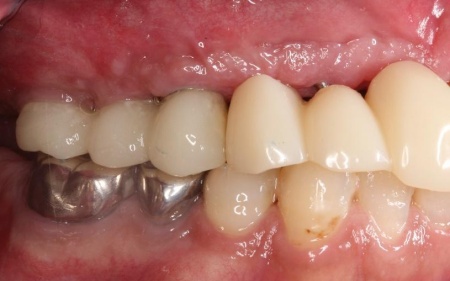

他院で治療を行った左下奥歯3本のインプラントは、土台をそのまま活かして人工歯だけ作り直し、噛み合わせを調整します。

左下奥歯1本、右下奥歯2本に装着されていた古い被せ物はすべて外し、ジルコニアクラウンと交換しました。